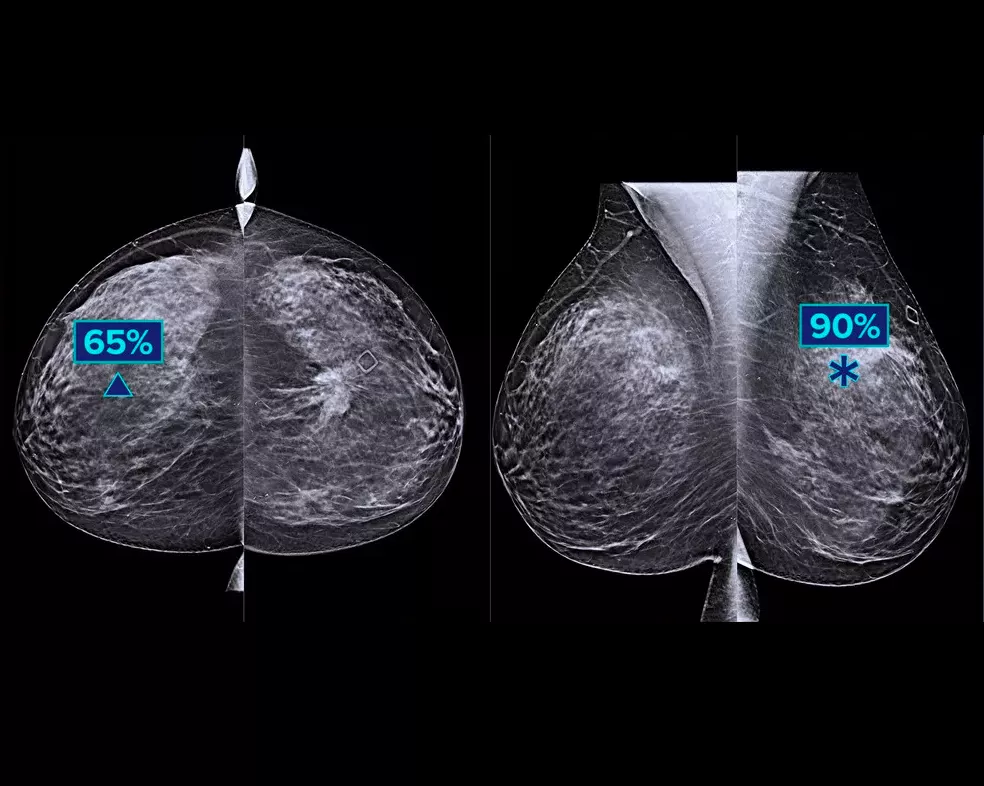

En deep-learning-algoritme designet til at hjælpe radiologers diagnostiske kapacitet og opdage brystkræft1-3 fra tomosyntesebilleder, der er optaget ved hjælp af Hologic Dimensions Mammography® systemer. Algoritmen lokaliserer læsioner, der sandsynligvis repræsenterer brystkræft, ved at søge i hvert snit af tomosyntesebilledsættet. Det mistænkelige område fremhæves til samtidig aflæsning på radiologens arbejdsstation for at bidrage til fortolkningen.

Algoritmen ser efter 3 hovedgrupper af mistænkelige læsioner: forkalkninger, masser, densiteter og forvrængninger og enhver kombination af disse læsioner. Output kan variere på forskellige læsearbejdsstationer.